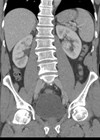

With the advent of widespread cross-sectional imaging there has been a surge in incidental detection of small renal masses (SRMs) and renal cell carcinoma (RCC) is now the seventh most common cancer in the UK. Whilst surgical excision for larger...